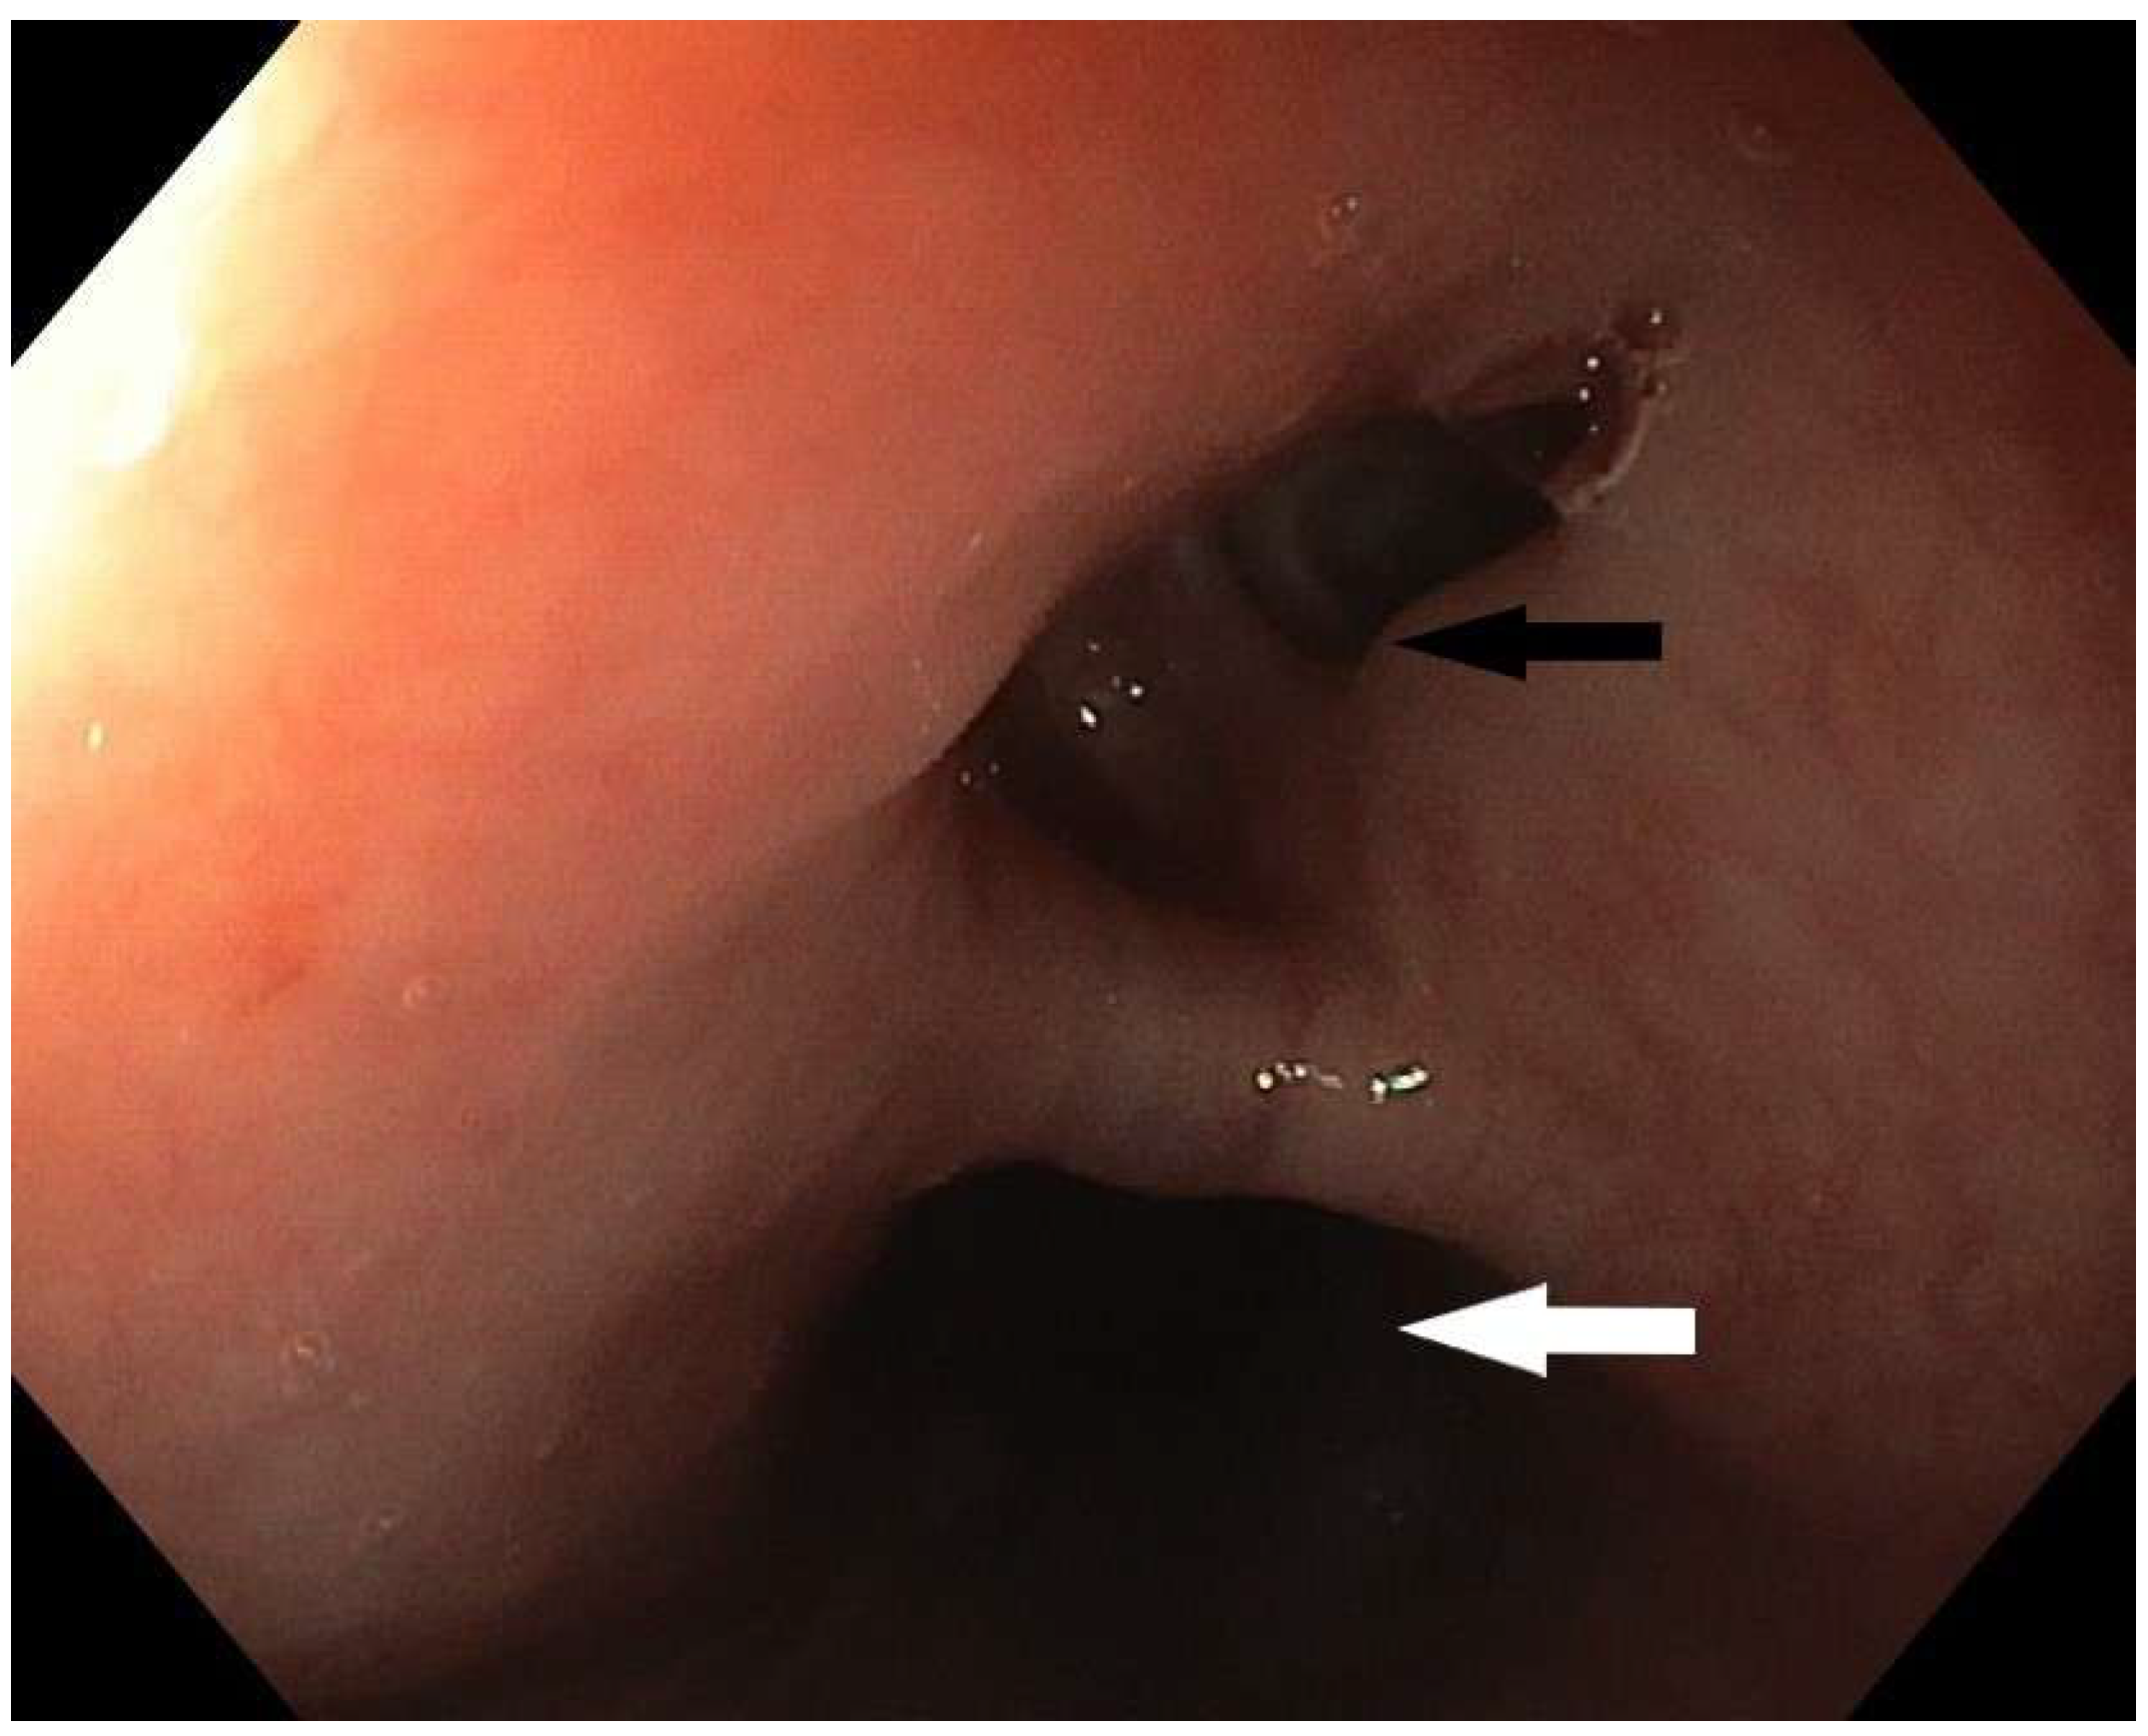

Figure 1. Upper gastrointestinal endoscopy in a female patient, 60 years old, revealed the presence of a fistula opening 20 cm from the incisors. This image shows the opening of the fistulous canal (black arrow) and the lumen of the esophagus (white arrow). The patient was admitted to the regional hospital for laparoscopic cholecystectomy. The prior day, ERCP procedure was performed, and a gallstone was removed from the main hepatic duct. Immediately after the initiation of the surgical procedure, and creation of the pneumoperitoneum, the patient experienced dramatic respiratory instability, a drop in oxygen saturation, and extreme gastric air dilatation, so the surgical procedure was abandoned. Liquid green output, highly suspicious for gastric content, was observed from the endotracheal tube. An emergency CT was performed, confirming the diagnosis of tracheoesophageal fistula. Two days later, the patient was admitted to the Intensive Care Department of the Clinic for Digestive Surgery, University Clinical Center of Serbia. The patient was intubated, sedated, and on continuous vasopressor stimulation. Tracheoesophageal fistula (TEF) in adults is usually an acquired condition, which can be further divided into benign and malignant TEF. Benign fistulas are mostly iatrogenic (post-intubation, post-surgery, post-radiation) [1]. Post-intubation trauma is responsible for approximately 75% of benign tracheoesophageal fistula cases [2]. The diagnostic modalities include contrast radiography, CT imaging, bronchoscopy, and upper gastrointestinal endoscopy. Upper GI endoscopy clearly shows a defect in the esophageal wall with a formed fistulous tract which was confirmed by a CT scan showing a pathological communication between the anterior wall of the esophagus and the initial part of the left bronchus. The fistulous tract has a maximum lumen width of about 6 mm (Figure 2). MDCT revealed esophago-tracheal fistula, with the ostium on the esophagus 11 mm of width, 6 mm opening on the tracheal wall, and fistulous tractus 6 mm in diameter.